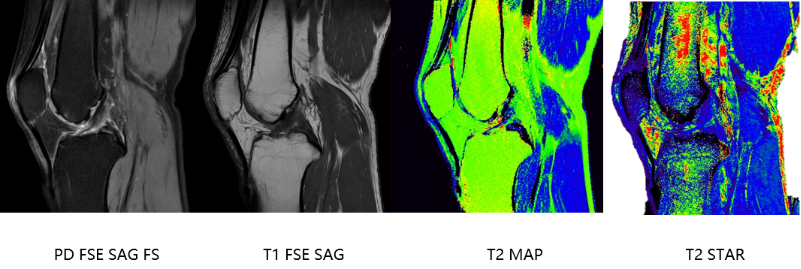

与此同时,uMR 780 作为 “软组织之王” 的优势,在高原高发骨关节病诊断中展现出变革性价值。其先进的定量 T2 mapping 技术,能无创探测关节软骨早期生化损伤,将大骨节病等退行性病变的预警窗口大幅提前。

优化后的成像序列可精准捕捉骨髓水肿等关键损伤信号,为病情评估提供可靠依据。这种无辐射、可反复检查的特性,尤其适合慢性关节病患者长期随访监测。

膝关节软骨损伤MAPS